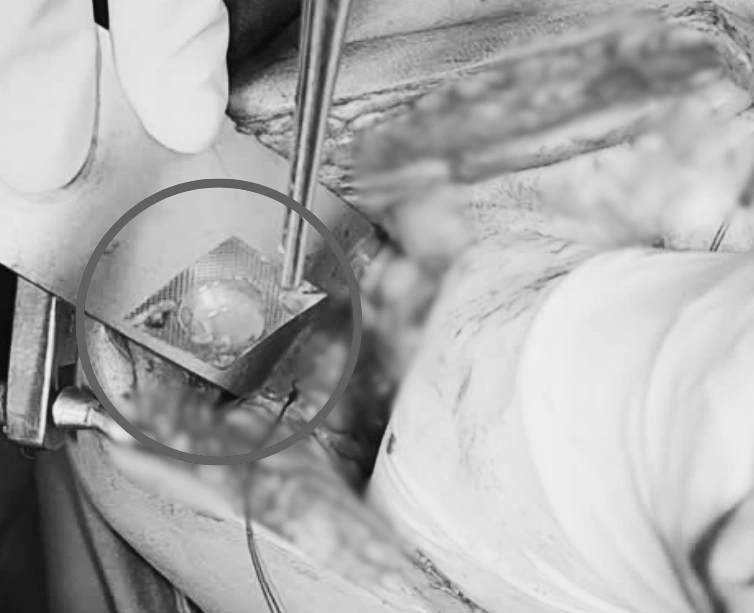

Trong quá trình phẫu thuật, thám sát thấy vùng van hồi manh tràng bị viêm cứng, xung quanh nhiều giả mạc bao phủ, có một lỗ thủng nhỏ và dị vật ngay manh tràng. Bác sĩ tiến hành mở lỗ tại manh tràng cách van hồi manh tràng khoảng 3 cm để lấy dị vật ra ngoài, sau đó cẩn thận khâu kín lỗ thủng, dị vật được xác định là một viên thuốc còn nguyên vỏ bao.

Viên thuốc được gắp ra khỏi manh trang bệnh nhân

ẢNH. BSCC